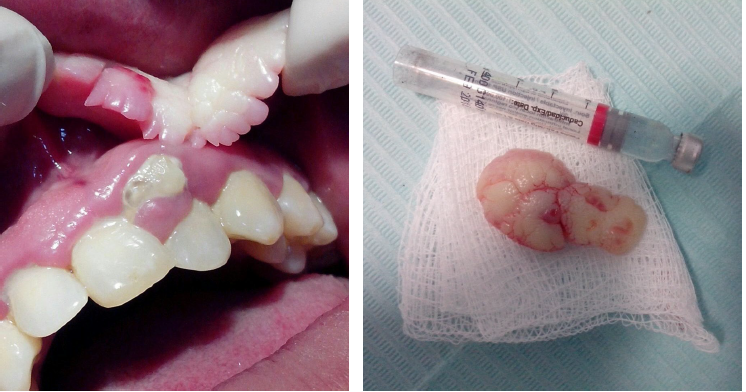

biopsy

the process of taking a sample of living tissue for histopathologic examination

gold standard for definitive diagnosis

tissue specimen is process into glass slides and histologic features are evaluated microscopically

biopsy methods

excisional biopsy

incisional biopsy

needle biopsy

fine needle aspiration

excisional bipsy

total removal of lesions, either as a surgical biopsy or a punch biopsy

representative sample of the lesion either as surgical biopsy or punch biopsy

using a large-bore needle

using a small diameter needle

biopsy and tissue processing

ten percent buffered formalin, as an ideal tissue fixative → tissue processor→ five micron thick section cute using a microtome→ staining the slides→ studying the slides under the microscope